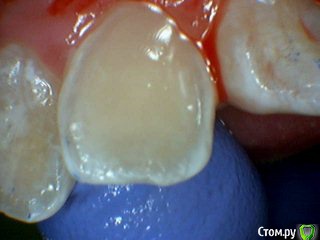

Давлетшин Опубликовано 13 июля, 2017 Поделиться Опубликовано 13 июля, 2017 Обидно понимаешь за детство, сообщений особо нет. подумать не над чем.два клинических случая. будут там пульпиты или нет? вот в чем вопрос. в одном случае пломба Витример в другом Эстелайт, без прокладок. Порядок фото несколько нарушен. Работаем над этим. Ссылка на комментарий

Mikhail_29_rus Опубликовано 17 июля, 2017 Поделиться Опубликовано 17 июля, 2017 Все будет хорошо , пульпит далеко Ссылка на комментарий

Dok22 Опубликовано 28 июля, 2017 Поделиться Опубликовано 28 июля, 2017 На всякий случай рентген контроль раз в пол года пару лет и проверка на витальность. Ссылка на комментарий